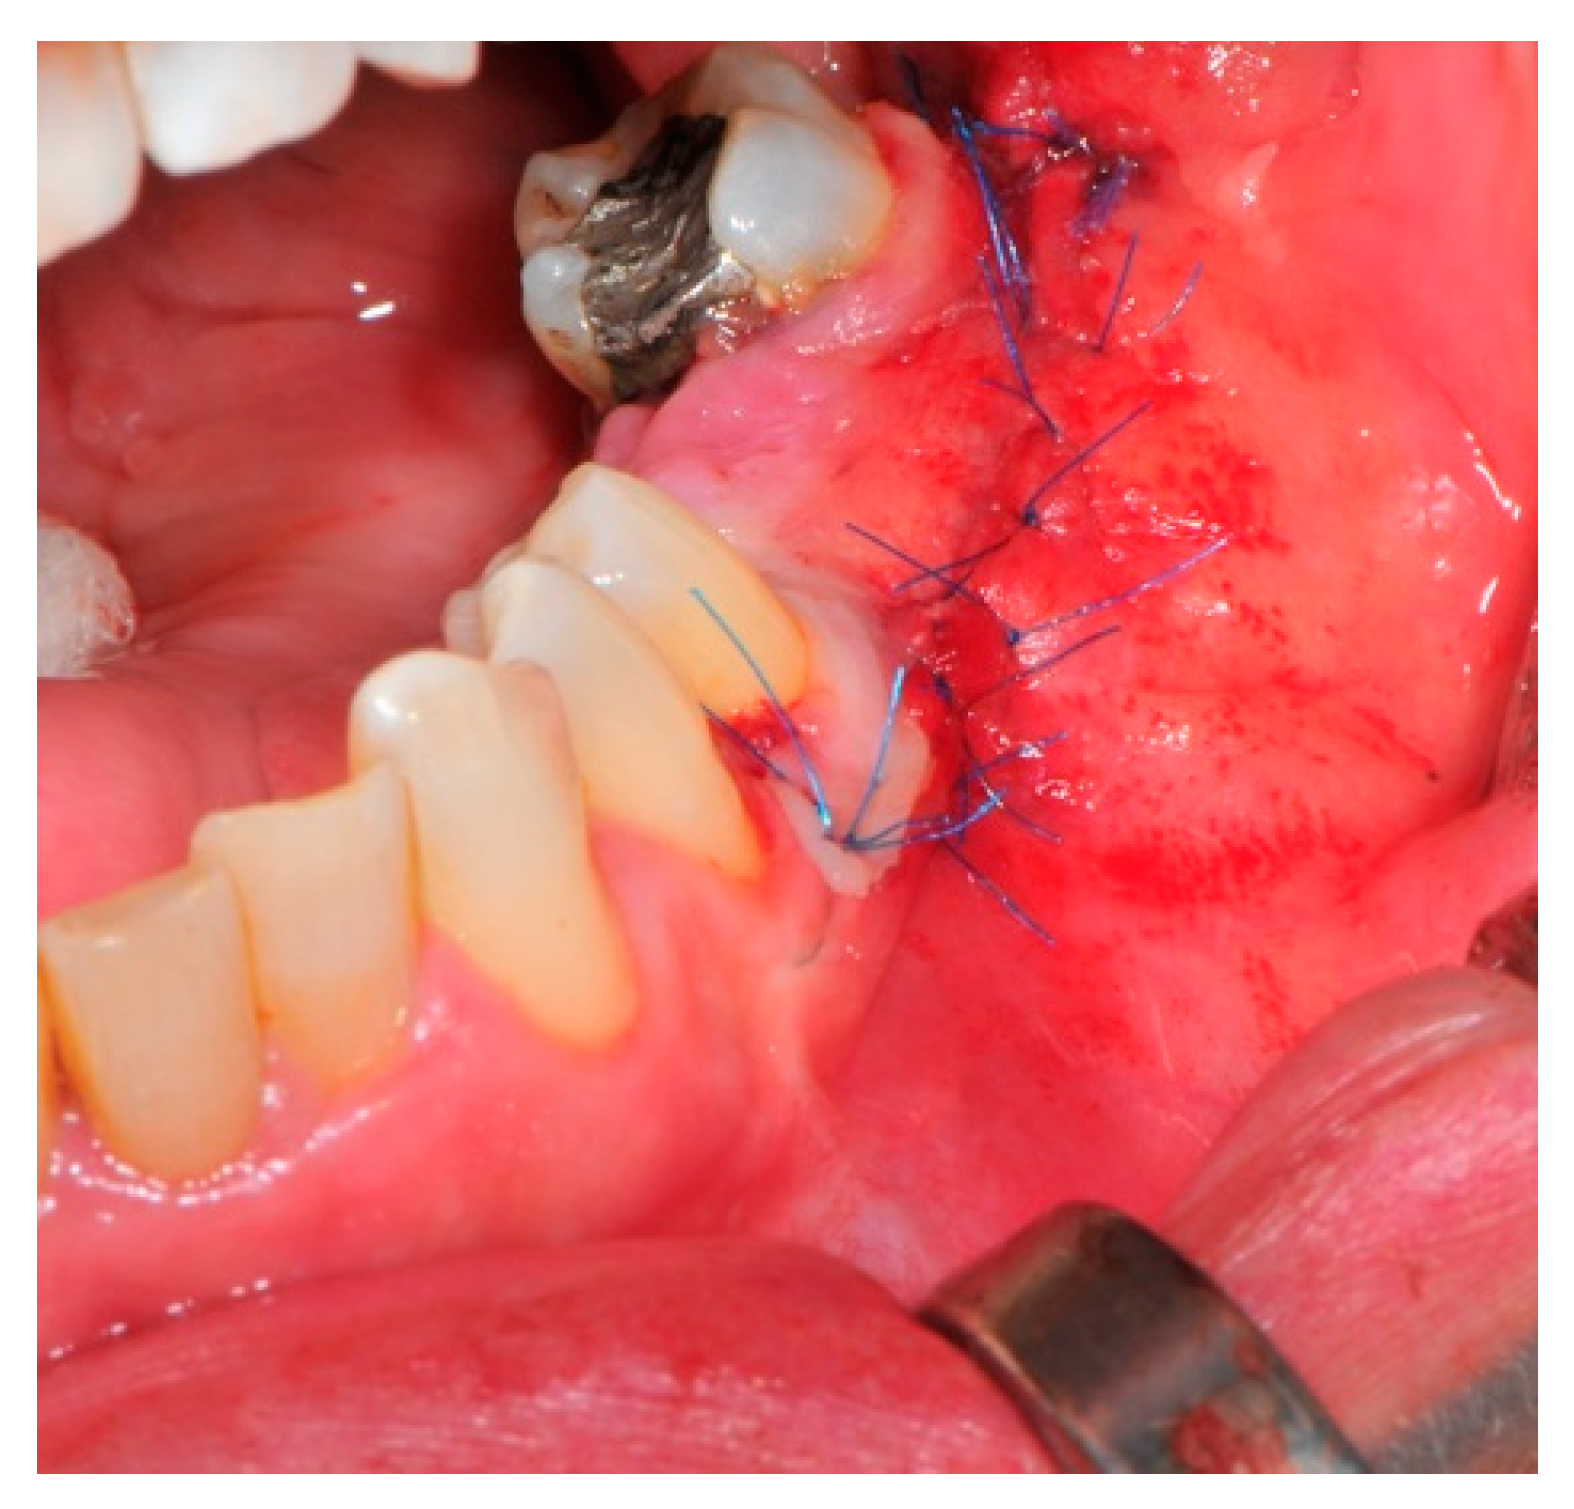

- Suture: Perfect closure is achieved with a first line of horizontal mattress sutures positioned 5 mm from the incision line and, subsequently, with single interrupted stitches connecting the edges of the flap. With this technique, the edges of the flap are reversed, putting the inner layers of the connective tissue in close contact with each other. The intimate connection between the layers of connective tissue forms a barrier that largely prevents the exposure of the membrane (Figure 12 and Figure 13).